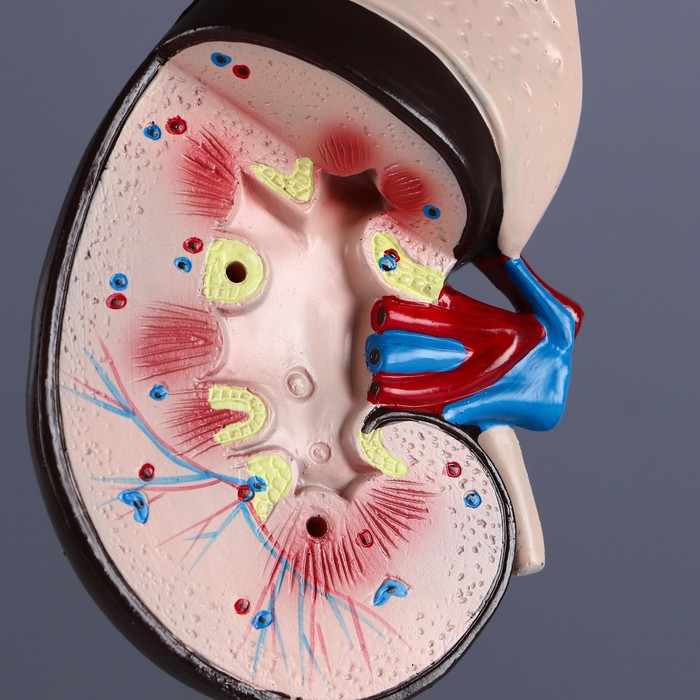

Анатомические модели